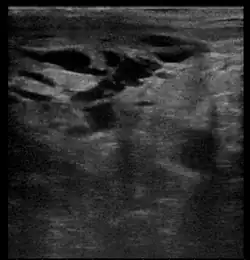

Breast ultrasound is the use of medical ultrasonography to perform imaging of the breast. It can be used as either a diagnostic or a screening procedure.[38] It may be used either with or without a mammogram.[39]

Diagnostic anatomic ultrasound looks at the anatomy whereas diagnostic functional ultrasound records information such as blood flow or tissue characteristics. A specific functional form of ultrasound is elastography which measures and displays the relative elasticity of tissues, which can be used to differentiate tumors from healthy tissue.[40] Recent studies have shown that shear wave elastography in primary invasive breast carcinoma could be useful for indicating axillary lymphadenopathy.[41]

Ultrasound is also used surgically. Specifically, an ultrasound-guided needle biopsy allows providers to see the needle so it can be directed toward the lesion of concern while avoiding other critical structures such as blood vessels.[40] Ultrasound-guided biopsies have also been shown to decrease re-excision and mastectomy rates in breast cancer. A recent study found 100% ultrasound localization with negative margins obtained in both non-palpable and palpable lesions at initial procedure. In line with this, intraoperative ultrasound guided breast conserving surgery is being increasingly used by breast surgeons worldwide[42]

Contrast-enhanced ultrasound (CEUS) imaging has also been researched and shows similar sensitivity to MRI in detecting breast cancer across lesions of similar size. Additionally, the combined use of MRI and CEUS in lesions > 20 mm has been shown to optimize the diagnostic specificity and accuracy in breast cancer prediction.[43]